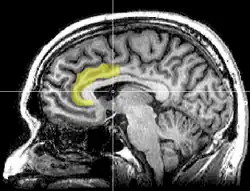

Unlike Freud's model where it was proposed that the energy for self control just came from "within" there is supportive research showing the areas of the brain that are linked to self control. It mainly happens from within the prefrontal cortex, in areas such as the anterior cingulate cortex.

Although all areas of the brain require blood glucose to function, there are certain areas that are more sensitive to the flow of glucose through the brain. Responses that require more effort or are a controlled response will require more glucose, same with higher executive functioning. This also explains why the whole brain does not stop working once the glucose falls, such as with self control, if an automatic, less effortful response is less sensitive to blood glucose, it will not stop functioning if there is a drop in glucose levels. However, these functions can not be over stimulated with excess glucose to produce some super self control (Galliot & Baumeister, 2007)